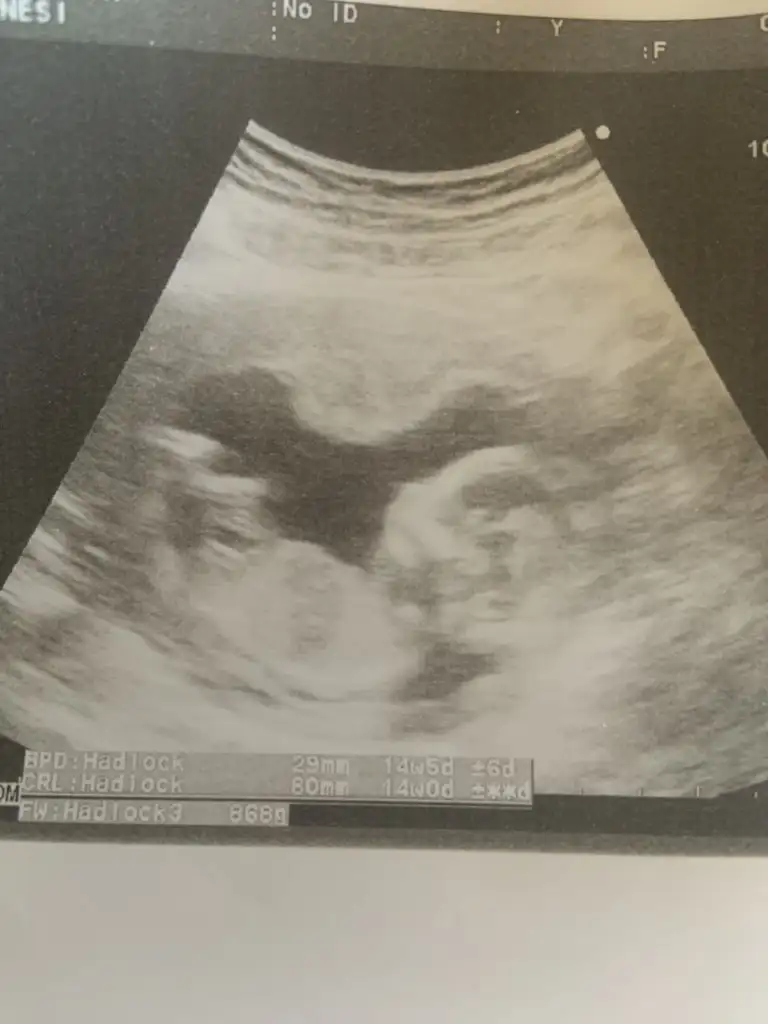

Yapısı erkek gibiBizimkinede bakar mısınız bir doktor kız dedi biri erkek burdada bir ara paylaşmıştım ama şimdide önünde kordon var yine öğrenemedim rica etsem anlayanlar bakabilir mi üç kızım var inşallah saglikli bir erkek istiyorum hayirlisiyla

Benimkinide yorumlar mısınYapısı erkek gibi

Çok erken en iyi 11 12 13 haftalar olmalı şimdilik kız yönünde ama yanıltabilir

Kız görünüyor